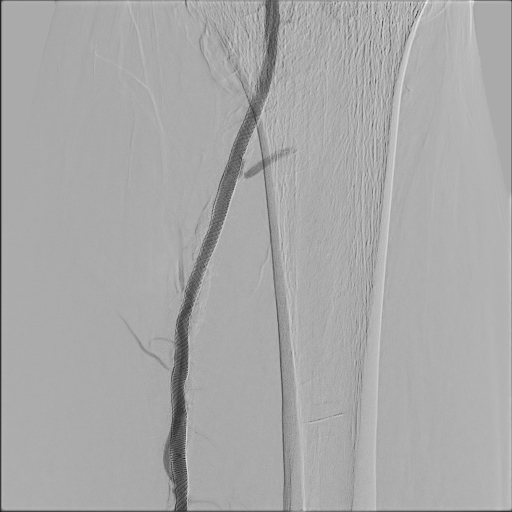

Owning to multiple stenosis and total occlusion, terumo wire cannot pass through the lesion. we ever use Connect wire, V-18 wire and even shift to Astato for calcified lesion with the assist of CXI. After several times attempt of antegrade wiring, the V-18 wire finally pentrate thrthrough the calcified lesion and advanced to distal popliteal artery. Finally the V-18 wire pass the lesion and balloon angioplasty was performed. Diffuse dissection with TIMI II flow was discovered after balloon angioplasty, thus we deployed Supera stent at SFA.Final angiogram showed acceptable result.

Despite multiple calcified lesion and totally occluded vessel length longer than 200mm, with the guidance of calcification and distal true lumen angiogram, we use crossover-antegrade approach to pass through the lesion with successful balloon angioplasty and stenting. Final result was TIMI III flow of distal limb and the patient's symptoms subsided.